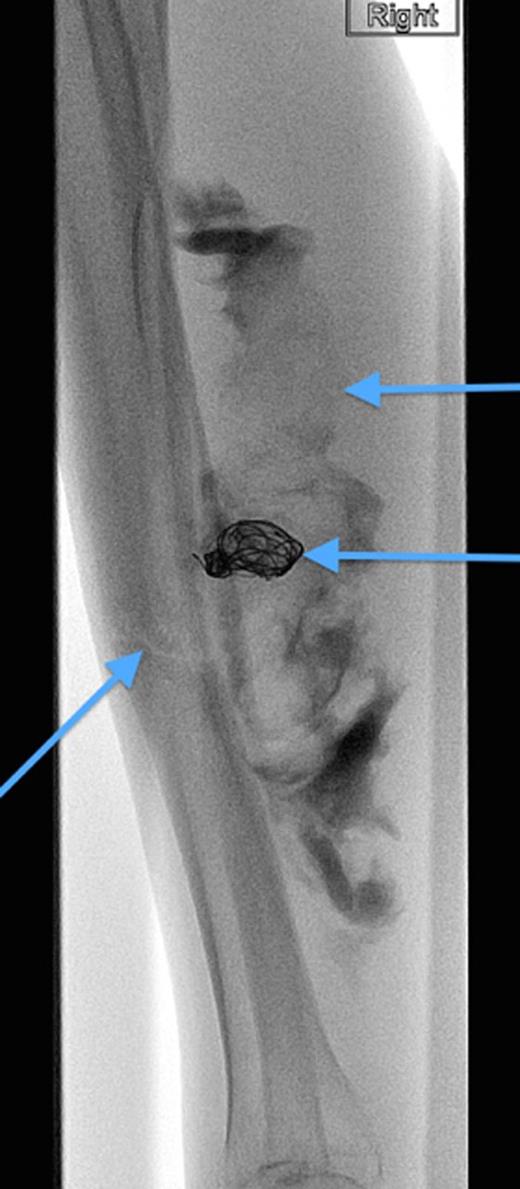

A 20-year-old man with no past medical history presented to the emergency department with non-displaced and closed transverse fracture of the left mid-tibial shaft and an intact fibula induced by a tackle during a football match. On examination, he had no neurovascular deficit and all crural pulses were palpable. His fracture was treated conservatively with a non-weight bearing above knee plaster cast later replaced by a below knee cast for a total period of 6 months. Upon examination during his attendance to the facture clinic, x-ray demonstrated no signs of fracture union. The subsequent magnetic resonance imagining (MRI) confirmed a nonunion of the fracture along with an ovoid 2.7 cm posterior compartment vascularized mass causing bowing of the interosseous septum with no evidence of avascularity of the bony margins (Fig. 1). This was confirmed to be a pseudoaneurysm originating from the PTA. An endovascular approach was adopted, and the pseudoaneurysm was injected with 2 ml of thrombin, filled with multiple coils and deployment of an angiography balloon (in the sac) (4 mm × 6 cm) for 7 min (Fig. 2). This resulted in complete cessation of the pseudoaneurysm with normal flow in the PTA (Fig. 3). The residual extravasated hematoma was later drained by an open approach. Follow-up x-ray (6 months) demonstrated complete union of the fracture site with no associated complications.

MRI images demonstrating the site, size and the origin of the PTA pseudoaneurysm.